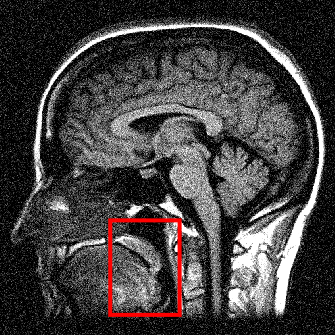

We display the noisy image and the reconstructed images from these three denoising methods in Fig. 8 111 Image retrieved from http://radiopaedia.org/ by Frank Gaillard.. To better understand the performance, we zoom in the selected part of the image and display them in Fig. 9.

We observe that the anisotropic TV suffers from the staircase artifact due to the fact that the TV is local operator. On the other hand, the reconstruction with TFV regularity has blurry effect on the edges. This is not surprising because the TFV is a non-local method and it is less edge sensitive than TV. Instead, the TV-TFV regularity avoids such artifacts and has a better reconstruction of both the edges and the overall image.

We also present the numerical results of different performance measurements in Table 3. The TV-TFV regularity shows better results in such measurements as well.

We display the ground truth image and the reconstructed images from the inverse Fourier method, the PCM-TV method and the PCM-TV-TFV method in Fig. 10.

We point out that the noisy image in Fig. 10 is obtained directly by inverse Fourier transform and we can see that the noise level is quite high in this case. Both the PCM-TV and the PCM-TV-TFV are able to produce more reasonable visual results. To see a deep comparison, we zoom in the red square part of Fig. 10 and present the approximation errors in Fig. 11.

We can see that the PCM-TV-TFV has a much less error than the PCM-TV model for the surface reconstruction.